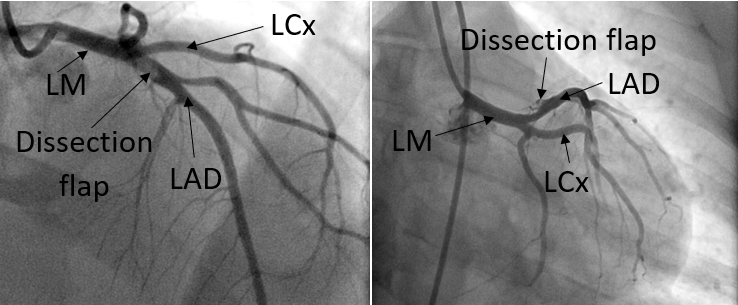

Several days later, the patient returned to the emergency department to complete the evaluation. He reported only one brief episode of chest pain at rest and acknowledged that he had not been taking his medications consistently. Repeat coronary angiography demonstrated a contained pLAD dissection without residual thrombus (Figure 3). Given the initial angiographic appearance of an occlusive thrombus, the interval resolution of thrombus, and the new appearance of the dissection after thrombectomy, the contained dissection was considered most consistent with an iatrogenic complication of the prior intervention rather than the primary etiology of the index event. No further coronary intervention was performed. The patient again elected to leave against medical advice and was instructed to continue guideline-directed medical therapy for coronary artery disease and heart failure with reduced ejection fraction.

Figure 3. Coronary angiogram one week after initial thrombectomy, showing a dissection flap in proximal LAD from two views.